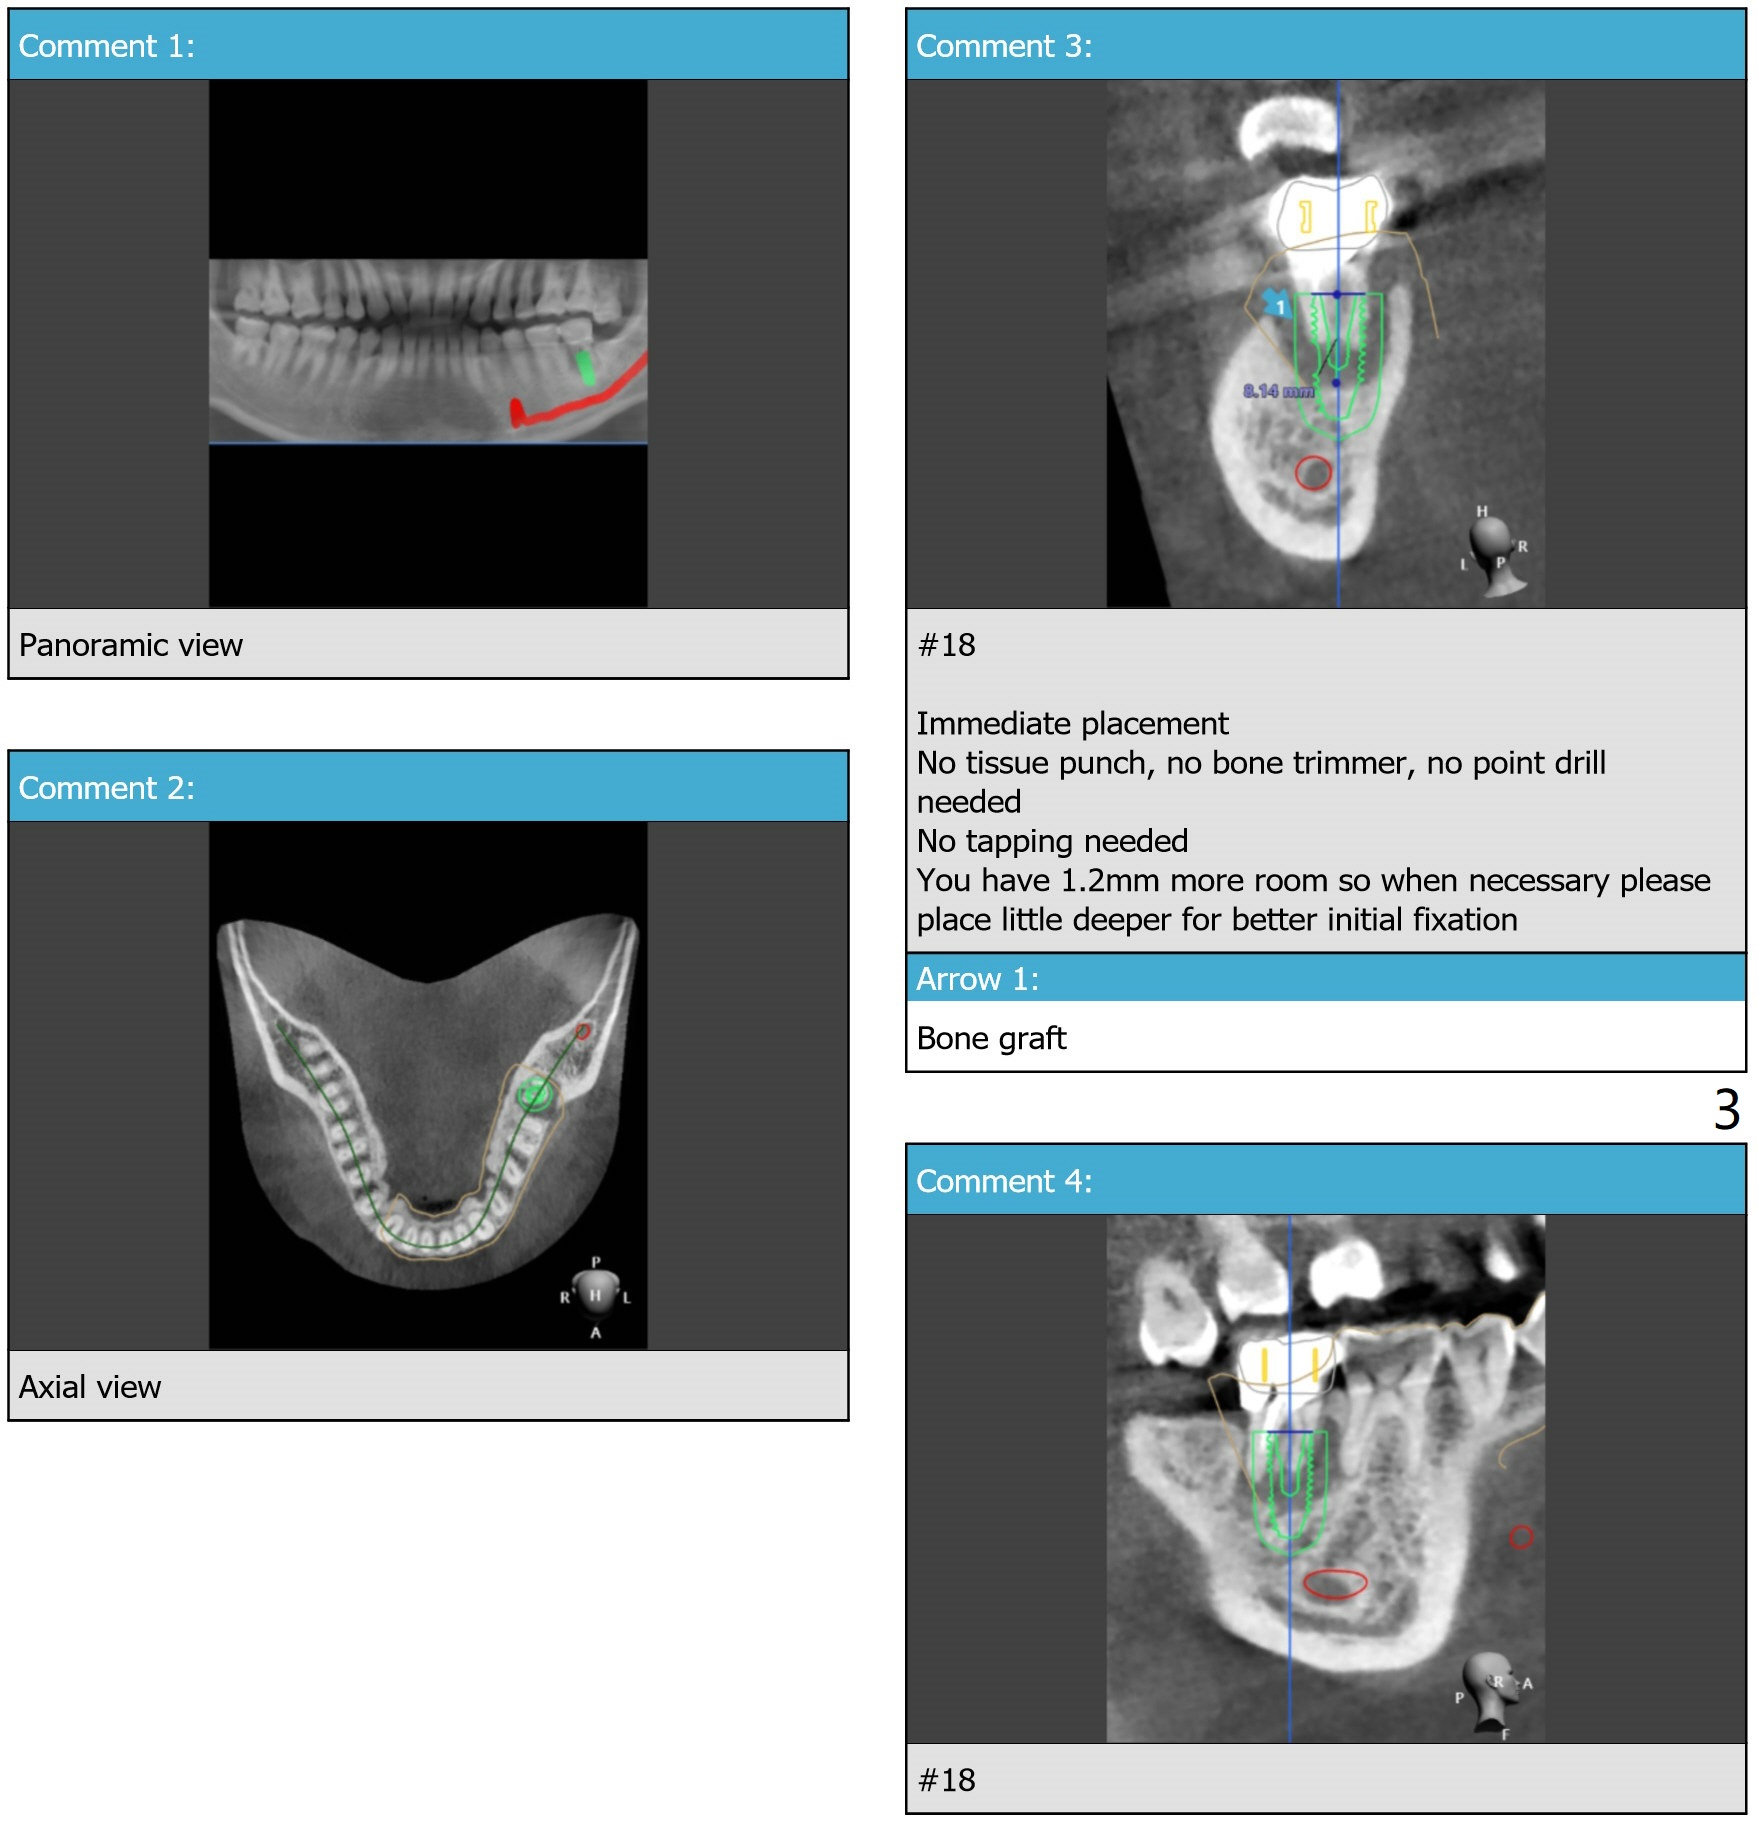

Xin Wei, DDS, PhD, MS 1st edition 10/30/2019, last revision 11/21/2019